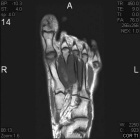

21 year old male with swelling and pain in left foot for six months

Zoom image: Radiological image Radiological image.